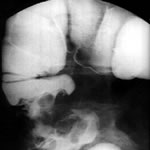

А вот я еще забыла я еще на всякий случай сделала и рентген толстого кишечника там тоже все ок небольшое опущение.У меня запоры и метеоризм но с запорами я справляюсь с помощью воды. Но вот эта боль меня замучила боль после дефекации в паху и в попу отдает в поясницу.Я уже совсем замучилась и о раке думала но исследования ничего не показали. Помогите !!!!!!У гинеколога была все в порядке небольшое воспаление. Узи мочевого там тоже воспаление.Сдавала посев мочи там нашли бактерию лечили но все по прежнему.Но мне кажется боли мои связаны с кишечником потому что после дефекации начинает болеть и геморрой вылезает начинает тянуть.

Сделали операцию, но опухоль не вырезали, наложили анастомоз. Недавнее УЗИ: ЭХО-признаки диффузных изменений печени и панкреас., ЖП, селезенка, почки без особенностей. чаговой патологии нет. Небольшое колличество жидкости в кармане Моррисона ( толщ.5 мм)По озорной рентгеннограмме с барием пат. уровней не определяется.